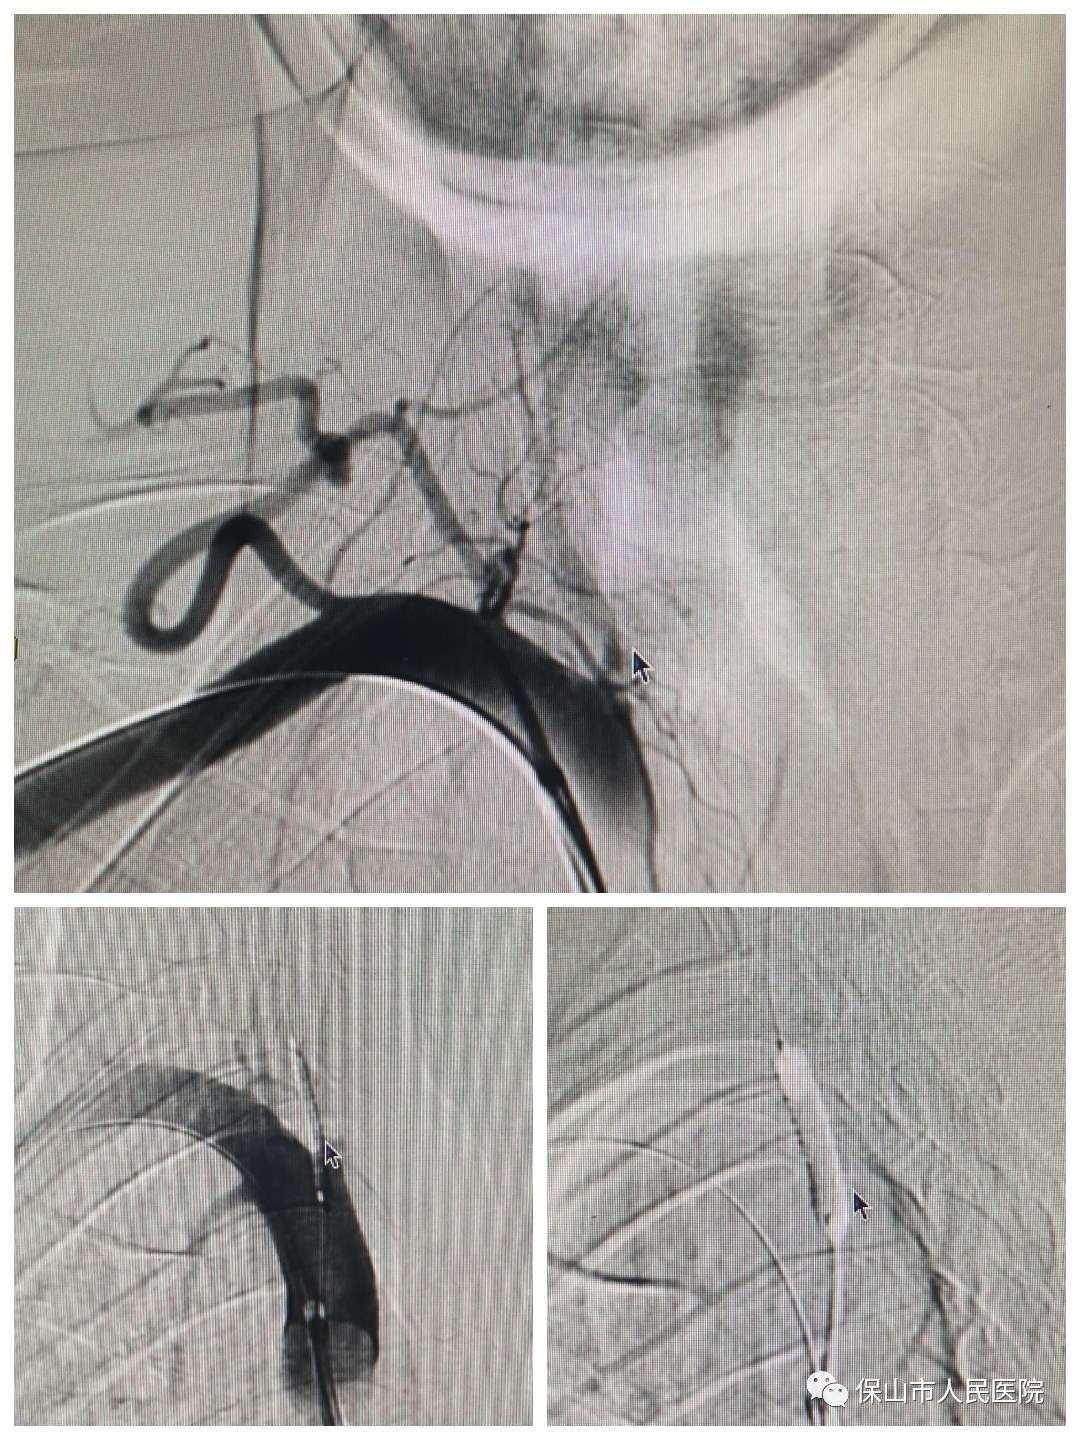

術中造影如上圖所示,箭頭標注的地方就是右側(ce) 大腦中動脈狹窄的部位,可以看到,狹窄程度大約在60%左右,雖然經過內(nei) 科治療後血流可以通過狹窄部位,但是狹窄部位後麵血管的血流速度較慢,大腦作為(wei) 需要大量血液快速交換的器官,患者右側(ce) 大腦半球的供血情況明顯是不理想的,而且患者隨時存在再次發生腦梗塞的風險,所以有必要進行支架植入術。

同樣的方法,通過導管和導絲(si) 的配合,將支架送到右側(ce) 大腦中動脈狹窄部位,確認好狹窄部位的位置後,釋放支架。

支架植入完成後,再次造影,可以看到,不僅(jin) 狹窄部位支撐開了,而且狹窄部位後麵的血管裏的血流速度也比手術前增加了。狹窄部位撐開,血流速度恢複,兩(liang) 個(ge) 條件都滿足了,手術也就圓滿結束了。